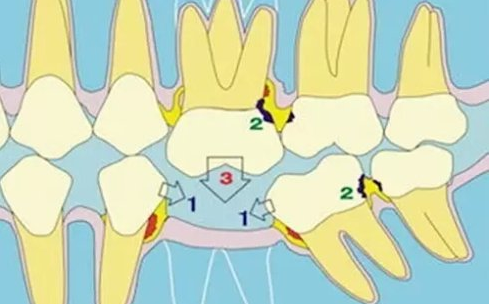

全口牙列处于一种动态平衡当中,单颗或者多颗牙齿缺失之后,余留下来的牙齿会发生一系列的变化:缺失牙的邻牙会往缺失牙方向倾斜,牙缝变大,造成食物嵌塞、细菌滋生和牙结石堆积,引起牙龈炎、牙周炎甚至造成邻牙牙齿松动。

如果下牙缺失,与其相对的上牙会逐渐伸长,甚至触碰到下牙牙龈。